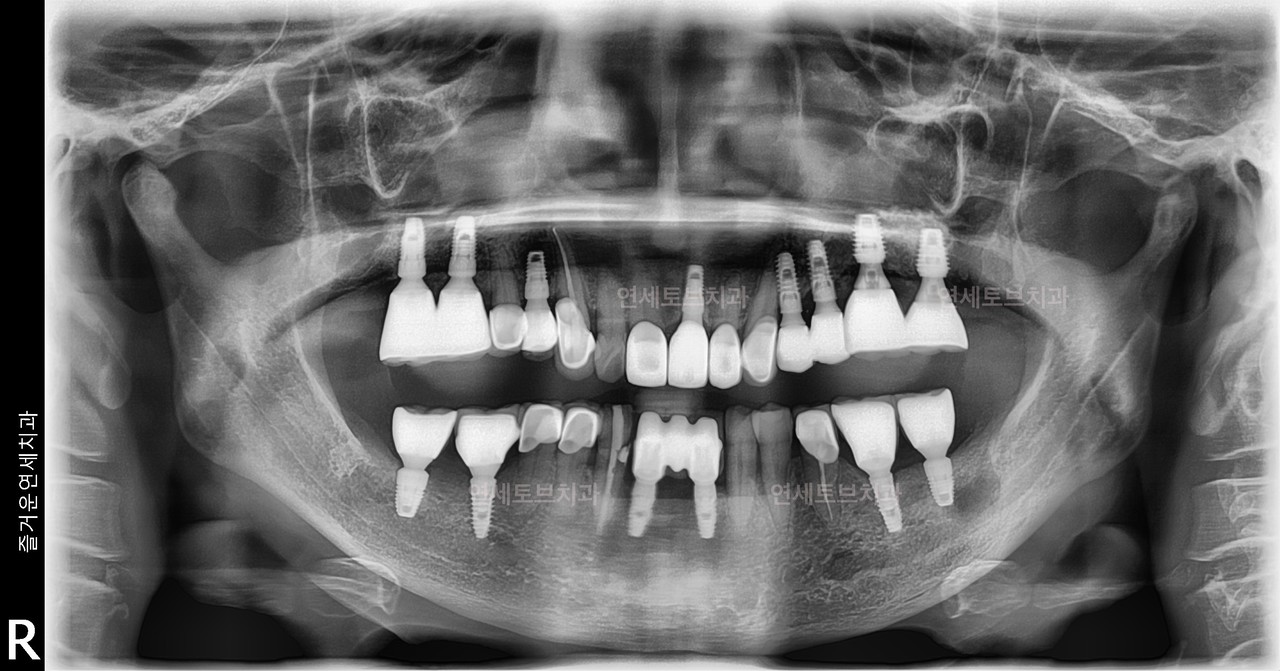

기존에 식립한 임플란트에 문제가 발생했을 때 이를 다시 치료하거나 교체하는 과정을 말합니다.

임플란트는 반영구적으로 사용할 수 있지만, 다양한 원인(잇몸뼈 흡수, 임플란트 주위염, 보철물 파손, 식립 위치 오류 등)으로 인해 재치료가 필요할 수 있습니다

기존에 식립한 임플란트에 문제가 발생했을 때 이를 다시 치료하거나 교체하는 과정을 말합니다. 임플란트는 반영구적으로 사용할 수 있지만, 다양한 원인(잇몸뼈 흡수, 임플란트 주위염, 보철물 파손, 식립 위치 오류 등)으로 인해 재치료가 필요할 수 있습니다